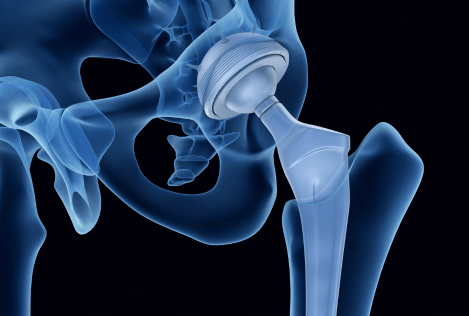

Metal Hip Implant Failure Lawyers

Hip replacement surgery is meant to improve your quality of life. But for thousands of patients, metal-on-metal hip implants have caused more harm than good. These defective devices can lead to severe pain, metal poisoning, mobility issues, and the need for revision surgeries — all due to poor design or manufacturing defects.